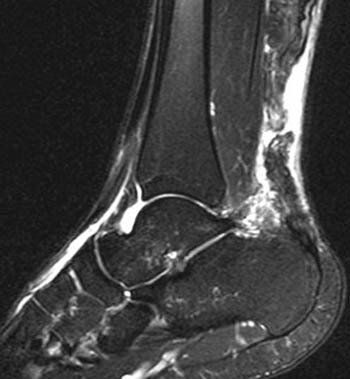

📌 El tendón de Aquiles

es el tendón más grueso y fuerte del cuerpo humano y desempeña un papel muy importante en la mayoría de los deportes y es particularmente vulnerable a la sobrecarga de la carrera y el salto reiterado.

⚽️ Las

roturas del tendón de Aquiles se dan con mayor frecuencia en deportes con balón que requieren cambios veloces de dirección y saltos rápidos y reactivos (p. ej. fútbol, tenis, pádel, etc).